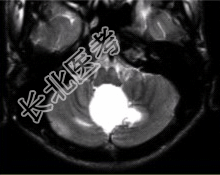

- [材料题] 男性,20岁。恶心、呕吐3d,剧烈头痛加重1d入院。MRI显示小脑下蚓部长T₁、长T₂信号影,病变可见结节状明显强化,如下图。

- 简答题1、请问该患者可能的诊断是什么?

- 简答题2、请问该病与VHL的关系是什么?